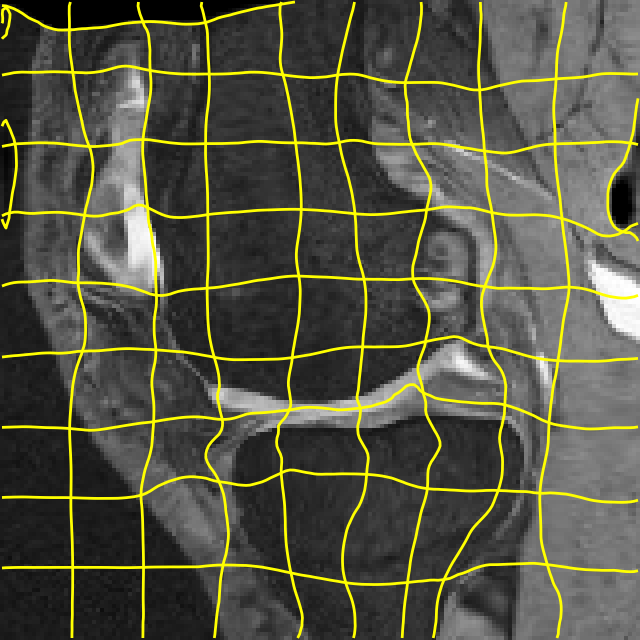

Moving

Target

Mono-0

Mono-5

DA-1

DA-5

Mono-200

Results: All trained networks are evaluated using Dice overlap scores between predictions and the manual segmentations for the segmentation network, or between the warped moving segmentations and the target segmentations for the registration network. Tabs. 1 and 2 show results for the knee and brain MRI experiments respectively in Dice scores (%). Fig. 2 shows examples of knee MRI registrations and brain MRI segmentations.

Qualitative results: DA achieves more anatomically consistent registrations than the mono-networks on the knee (Fig. 2) and Brain MRI samples (see supplementary material).